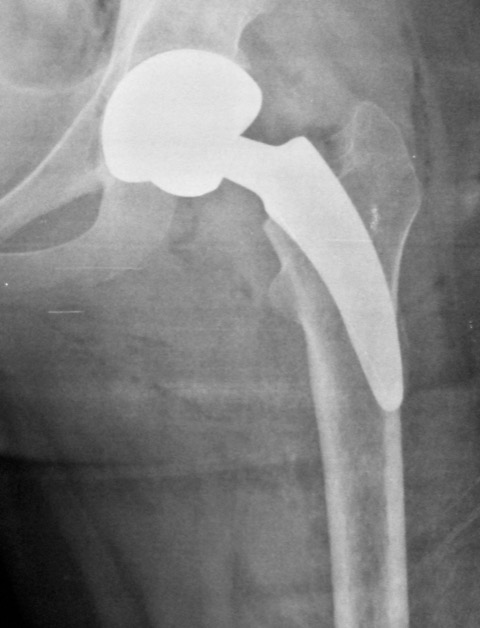

Reemplazo total de cadera con un tallo corto no cementado tipo 2B: resultados a los 2-5 años de seguimiento. [Total hip replacement with a short cementless stem type 2B: Results of 2 to 5 years of follow-up]